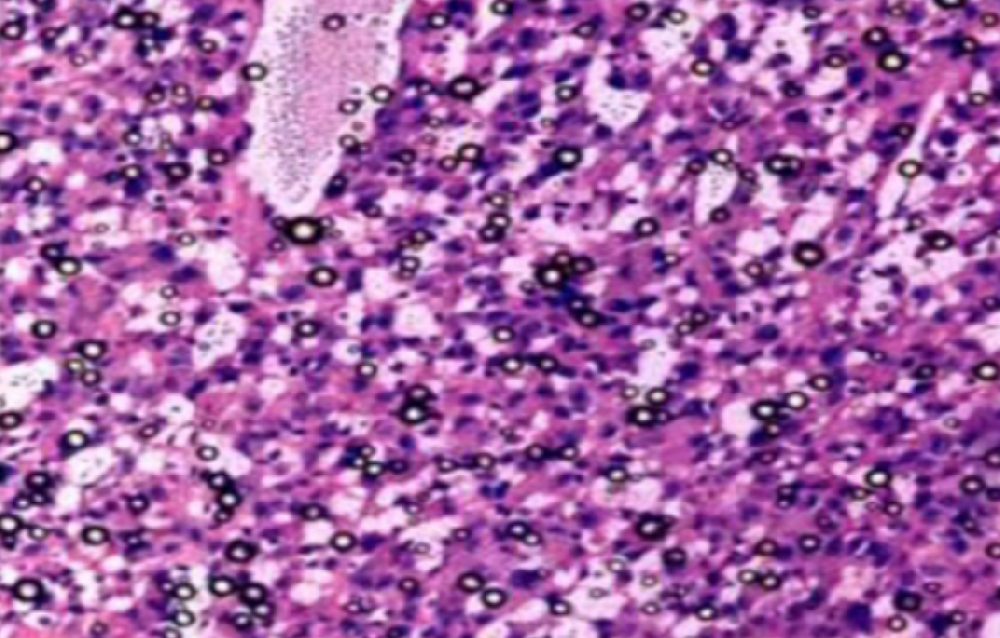

形成原因:切片经梯度乙醇处理后没有完全脱水,导致二甲苯透明、中性树胶封固后残留大量水分。 解决方法:首先移去盖玻片,用二甲苯溶解封固剂如中性树胶,再将切片置入无水乙醇内,待切片重新脱水完全后,用二甲苯透明处理,中性树胶封固。要注意所有用于脱水和透明的液体,在使用一定时间后,应及时更换。 二、细胞核呈红、棕色 形成原因:苏木精染色液过度氧化,切片在苏木精染液染色后返蓝不足。 解决方法:每次染色之前检查苏木精染色液的染色能力,发现苏木精染色液氧化过度应及时更换。此外,切片经苏木精染色后,要给切片以足够的蓝化时间,蓝化过程可用流水、温水、弱碱性溶液(如稀氨水或0.2%碳酸氢钠)等处理。 三、切片在脱蜡后出现大片白色斑点 形成原因:由于烤(烘)片温度太低,切片上的组织蜡膜在脱蜡前没有充分烤(烘)融化。或是因为切片在二甲苯液中停留时间不足,或二甲苯使用过久,造成的脱蜡不彻底。 解决方法:若是由于切片烤(烘)温度低所致,可以先用二甲苯去除切片上的封固胶,然后重新用二甲苯脱去切片上的石蜡,再进行后续染色。若是由于切片在脱蜡的二甲苯中停留时间不足或脱蜡二甲苯使用过久浓度不足所致,则需将切片退回到二甲苯中,停留较长时间,或更换二甲苯液体重新脱蜡,再入乙醇重新脱二甲苯,入0.5%盐酸水溶液褪色后,重新HE染色。 四、细胞核苍白暗淡,即苏木精染色太淡 形成原因:切片在苏木精染色液停留时间太短;苏木精染色液过度氧化,失去染色能力,不能再继续使用;分化步骤处理时间过长;固定不及时。此外值得注意的是,若骨组织细胞核暗淡,大多是脱钙过度造成的。 解决方法:切片重新染色。如果组织在酸性固定液(如Zenker、Bouin)或非中性缓冲甲醛液固定时间过长,细胞核染色能力将减弱,需增加其在苏木精染色液的时间,或用一些方法增加组织的嗜碱性,以改善细胞核的着色。例如,上述组织玻片可以使用Weigert铁苏木精染色液。如果组织是用Zenker液固定的,可将切片脱蜡后放在5%碳酸氢钠溶液3~4h,流水冲洗5min后染色。如果组织是用Bouin液固定的,可将切片脱蜡后放在5%碳酸锂1h,流水冲洗10min后染色。 五、细胞核过染,苏木精染液占据了细胞质 形成原因:玻片在苏木精染色液停留时间过长,或是切片太厚、分化步骤时间太短。 解决方法:如果不是因为切片太厚(用显微镜仔细上下微调,只有一二层细胞核层次),就需将切片进行脱色、漂白、重新染色,适当调整染色和分化时间。但如果确定是由于切片太厚导致的细胞核过染,则需要重新切片。 六、伊红着色淡 形成原因:可能是伊红染液pH值大于5,也可能是蓝化液残留过多,切片太薄,或是切片经伊红染色后在乙醇脱水时间过长。 解决方法:检查伊红染液pH值,必要的话,用乙酸将其调节在4.6~5.0之间,从而使伊红染色色彩艳丽。此外,确保每次蓝化步骤完成后,使用的弱碱性溶液被充分洗去,玻片上没有残留的弱碱性溶液。最后,检查切片的厚度,且脱水时不要让切片在低浓度乙醇中停留时间过长,因为含水多的低浓度乙醇会将切片伊红的颜色分化掉。 七、细胞质过染、分色不足 形成原因:伊红染色液浓度太高,特别是存在焰红燃料、四溴四氯荧光素钠。切片在伊红染色时间过长,或是切片在伊红染色后经乙醇脱水步骤时时间太短,而使乙醇分化伊红的作用不能产生,都能够使细胞质过染。 解决方法:适当稀释伊红染色液,减少伊红染色时间,或使切片在乙醇脱水等步骤时,停留时间相对均匀。同样,也要检查切片的厚度是否合适。 八、切片中出现蓝黑色沉淀物 形成原因:苏木精染色液中的金属膜黏附在玻片上。 解决方法:染色前仔细过滤苏木精染色液,建议使用半氧化苏木精染色液,如Gill苏木精染色液,可以避免过多的金属膜产生。 九、光镜下切片某些区域难以聚焦 形成原因:盖玻片上可能有封固切片的封固剂。 解决方法:移去盖玻片,重新用干净的盖玻片封片。检查切片封片方法,是人工手工封法,还是机器自动封法,如有问题及时调整。 十、封固剂从盖玻片与载玻片之间的缝隙回缩 形成原因:盖玻片弯曲或不平整,或是封固剂含二甲苯过多,稀释过度。 解决方法:移去盖玻片,重新找一张盖玻片,用干净的封固剂封片。如用手工封片法,保证在封固结束时,封固剂容器盖子为紧闭状态。且尽量使用小的容器盛装封固剂,一旦封固剂太黏稠,就可以选择废弃。 十一、细胞核呈灰蓝状态 形成原因:可能由于组织处理温度过高、过热,在液体石蜡中停留的时间过长。或是固定时间太短后,直接在高浓度的乙醇中进行了脱水处理。 解决方法:理论上来说,仅在组织浸蜡步骤才进行加热,组织不能在热蜡液中停留太久。如果由于某些原因不能进行下一步包埋处理,可将组织连同塑料包埋盒一并放置在室温空气中,冷却凝固,以备包埋。待需要包埋时再重新加温直至石蜡融化即可。组织在处理前必须确保固定良好,脱水最好能从低浓度的乙醇开始。 十二、类色素的点状结晶和黑色光滑细胞核 形成原因:这种裸核改变是因为切片封片前放置在空气中的时间太长,以至于二甲苯挥发,切片干燥。 解决方法:移去组织切片上的盖玻片和封固剂,重新处理。将切片水洗数分钟,然后重新脱水、透明、封固。封片过程中要保持组织切片的轻度湿润,尽量不要让其干燥。 十三、染色过淡或过浓 解决方法:如果染色过淡,可以增加染色剂的浓度、延长染色时间或更换新鲜的染色剂;如果染色过浓,则应减少染色剂的浓度或缩短染色时间。 十四、切片出现叠加褶皱 形成原因:新购买的玻片洁净度不够、用镊子撑开切片时操作不够熟练未能平整伸展,或玻片表面有油脂,切片粘贴不牢。另外,烤片时间不足、烤片温度过低或切片过厚造成切片脱落,都会造成重叠或有皱褶的情况。 解决方法:新购买的玻片最好能用硫酸清洁液浸泡一晚,然后流水冲洗干净。在适宜的温度下烤片时间宁长勿短,保证有充足的烤片时间和温度。另外,切片刀要锋利,才能切出厚薄适宜的切片,保证切片不会因为过厚而脱落。 十五、组织残缺不全或有刮划痕迹 形成原因:组织残缺不全是由于切片时修整蜡块时深度不够、组织没有全部暴露于切面。切片的刮划痕迹是由于切片刀的刀锋有缺口、包埋的组织有异物,或是钙化组织、骨组织及包埋石蜡有沙粒造成的。 解决方法:修整蜡块时保证组织块全部暴露于切面,切片时保证切片刀的锋利没刀口。同时在组织取材时去除手术异物和钙化组织。最后,骨组织要完全脱钙,这样可以保证切片的完整和平整美观。 *注:由于实验中导致结果出现误差的原因多种多样,以上内容仅供参考,具体根据实际情况进行判断。